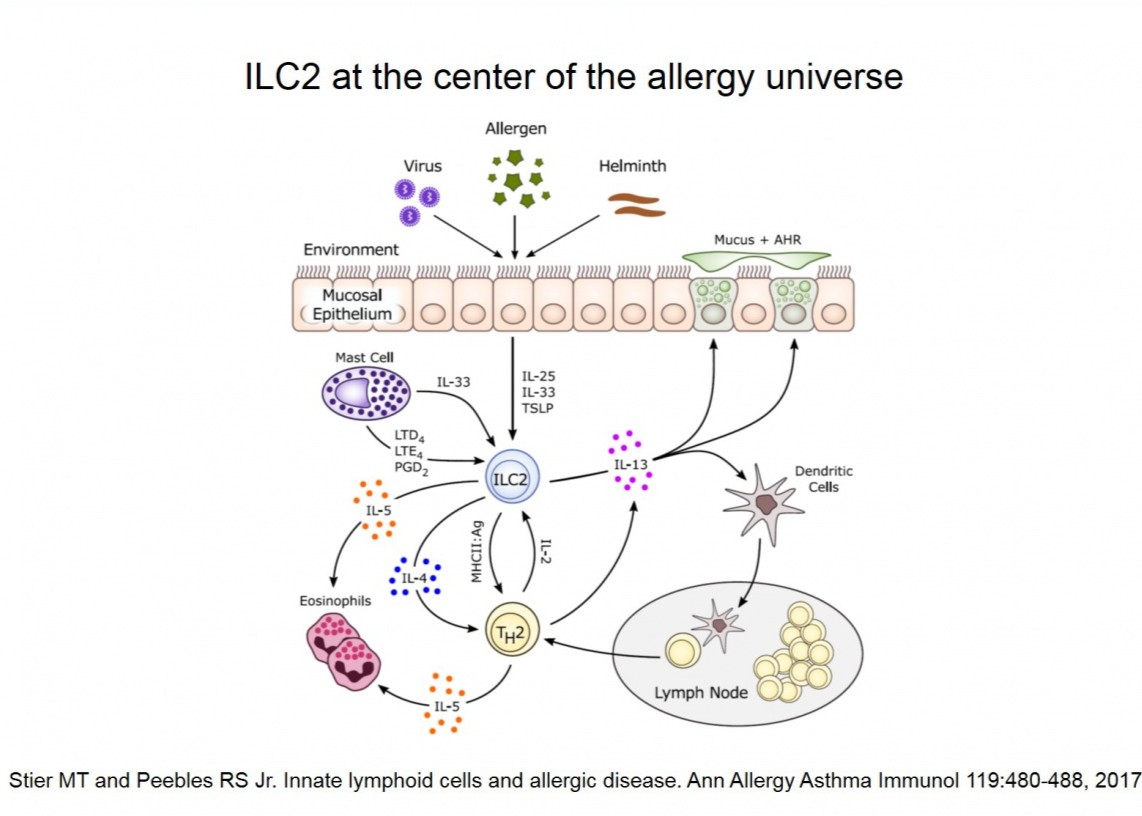

Our lab has a particular interest in the interaction of allergic disease and respiratory syncytial virus in causing airways responsiveness. While we are interested in studying host immune responses to both allergens and viruses, we are particularly interested in the contribution of group 2 innate lymphoid cells (ILC2) as an initiator of lung inflammatory responses.

ILC2 at the center of the allergy universe